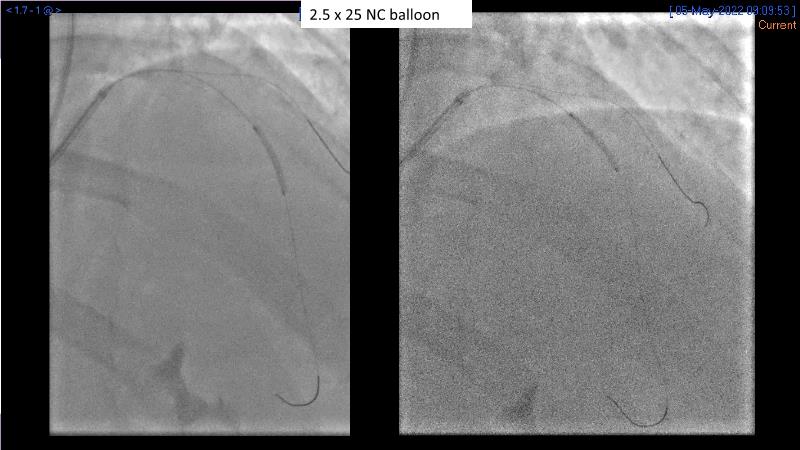

Sirolimus coated balloon: expanding the scope of coronary artery disease treatment

Consult this session to understand the technology and scientific evidence of the novel sirolimus drug-coated balloon, to learn its utility for PCI in a variety of lesion and patient subsets and to understand the evidence and outcomes in real-world patients.

- To learn the utility of the DCB for PCI in a variety of lesion and patient subsets